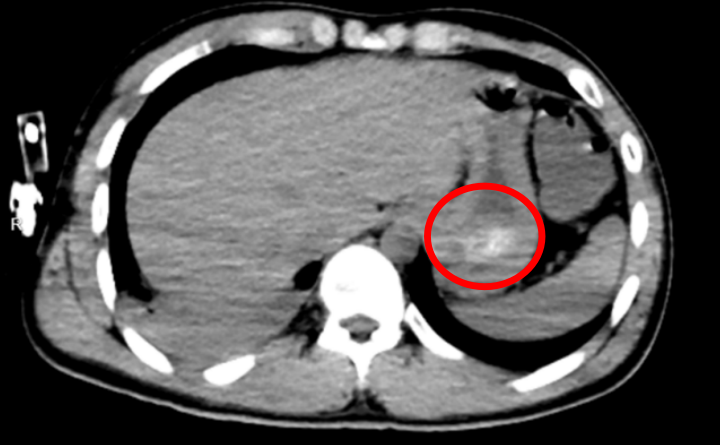

经全腹CT检查证实,林浩胃底存在大量团块状高密度影,也就是常规洗胃无法清除的“药石”,同时胸部CT显示其双肺出现渗出性病变,已引发吸入性肺炎。医生解释: